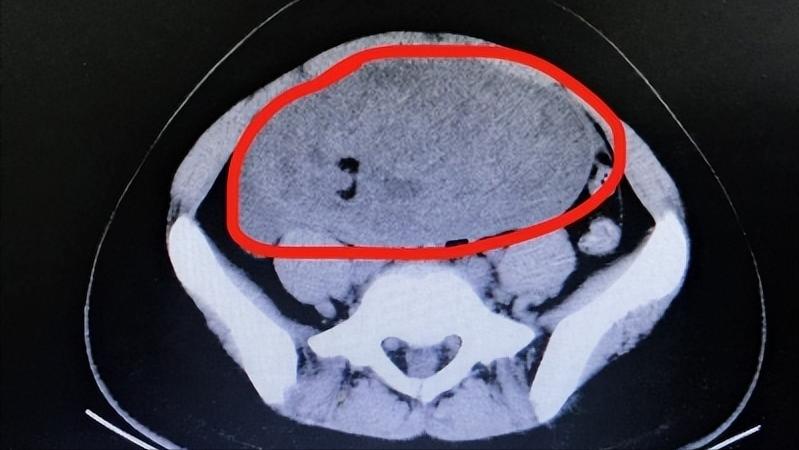

除此之外,女性长期腰痛不要以为是月经期原因,还有可能是盆腔肿瘤引起的。盆腔肿瘤导致腰部疼痛外常有不同程度的下腹痛,因为盆腔肿瘤中的肿瘤细胞不断增长会压迫腰部神经,导致出现腰部疼痛的现象,还可能因为癌细胞不断浸润、占据腰部神经细胞造成腰部疼痛。

所以,当女性出现腰部疼痛时,不要大意,要排除因妇科疾病导致的腰痛,进一步明确病因,进行对症治疗。

盆腔肿瘤会导致腰痛外,还要注意其他的症状。盆腔肿瘤早期会出现盆腔积液、积脓,患者盆腔及周围组织产生包块样肿物。是因为肿瘤细胞不断侵入盆腔,压迫盆腔内血管导致血液流通不畅。

此外,还会出现下腹部坠痛、月经紊乱、阴道少量流血的症状。因为肿瘤的生长会刺激卵巢的发展,造成机体内分泌紊乱,会导致月经不规律,进而造成阴道少量出血的现象。